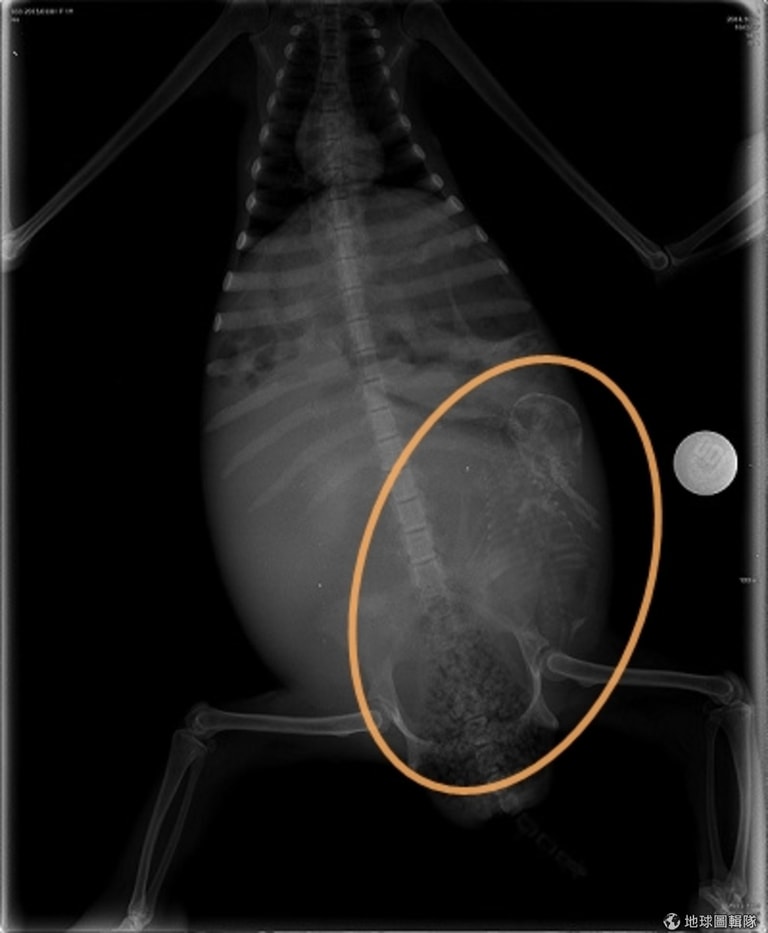

樹懶寶寶在媽媽體內的位置不利生產。 取自ONE GREEN PLANET

KSTR工作人員注意到樹懶有抽搐的情況,而且懷孕了。他們觀察樹懶媽媽的子宮收縮情況,但經過24小時仍沒有任何動靜,KSTR的經理Trull到動物醫院尋求幫助,才知道樹懶寶寶在媽媽體內的位置不利自然生產,Trull於是決定動刀,幫樹懶媽媽保住小孩,這是人類首次幫樹懶寶寶剖腹產。